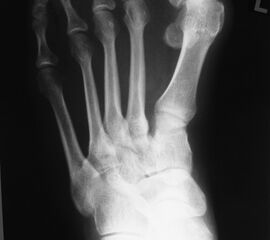

Röntgenaufnahme des Fußes (unter Belastung) in dorsoplantarem, seitlichen und schrägem Strahlengang (Abb. 1a-c).

Beurteilung des ersten Intermetatarsalwinkels (IMA), des Hallux valgus Winkels (HVA), des distalen (Distal Metatarsal Articular Angle, DMAA) und proximalen Gelenkflächenwinkels der Grundphalanx (Proximal Phalangeal Articular Angle, PPAA). Möglicherweise muss die Arthrodese des TMT-1-Gelenks mit weiteren distalen Eingriffen zur Korrektur des Gelenkwinkels kombiniert werden (z.B.: retrokapitale Osteotomie oder Grundphalanxosteotomie).

Zur Vollansicht bitte die Bilder anklicken.

Abbildung 1a

Abbildung 1b

Abbildung 1c